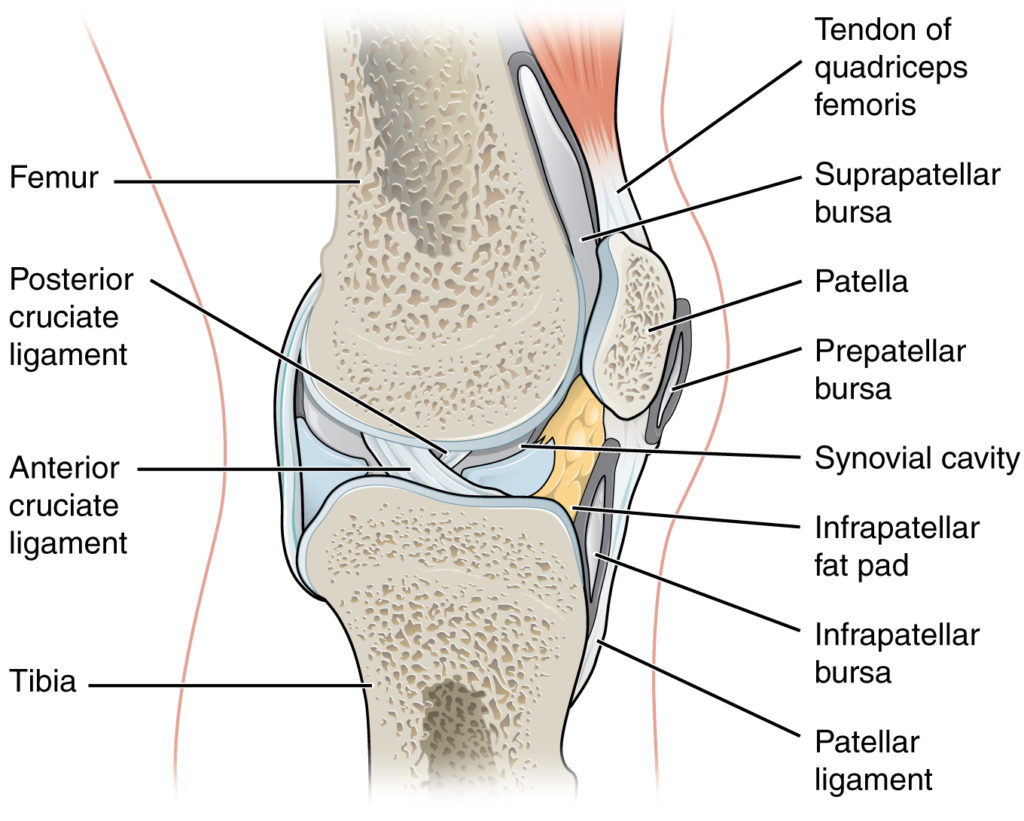

A knee joint effusion is usually radiographically appreciable as expansion of the suprapatellar bursa. This bursa usually contains a small amount of fluid and can often be seen as a thin, slightly radiopaque, finger-like projection situated posterior to the patella, separating the prefemoral and quadriceps fat pads.

In about 84% of people, the suprapatellar bursa is contiguous with the joint itself, however in the remainder of the population, there is a full septum between bursa and the joint. That said, given that the joint capsule extends proximally to the patella, even the minority of patients with full septation may have a radiographically appreciable effusion which pushes the patella anteriorly and bulks out the suprapatellar space with radiodense fluid.